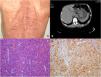

Un hombre de 65 años presentó dolor abdominal y pérdida de peso durante un periodo de 3meses. Sus antecedentes médicos incluían hipertensión y neurofibromatosis tipo1 (NF1). El examen físico fue notable por múltiples nódulos cutáneos y manchas color café claro en la piel distribuidos en todo el cuerpo (fig. 1A). En endoscopia gastrointestinal superior y tomografía computarizada abdominal se observó una masa tumoral originada en la pared anterior del antro gástrico, con un patrón de crecimiento intraluminal (fig. 1B). El paciente fue sometido a una gastrectomía distal subtotal. El examen histopatológico reveló un tumor de tipo célula epitelioide (fig. 1C) con >10 mitosis por 50 campos de alta potencia. Los exámenes inmunohistoquímicos fueron positivos para tumor celular de CD117/KIT (fig. 1D) y CD34. La NF1 (enfermedad de von Recklinghausen) es una condición autosómica dominante que ocurre en uno de cada 3,000 nacimientos. Los tumores de estroma gastrointestinal (TEGI) son tumores mesenquimatosos que son la manifestación gastrointestinal más frecuente de la NF1. El yeyuno proximal es el sitio más común de los TEGI en pacientes con NF1, y estos tumores tienden a ser múltiples. Los TEGI gástricos asociados a NF1 son eventos extremadamente raros y se han reportado menos de 20 casos a la fecha. El tratamiento de primera línea es la resección quirúrgica de márgenes microscópicos libres de enfermedad y de pseudocápsula intacta. En TEGI asociada a NF1, las mutaciones KIT y PDGFRA están frecuentemente ausentes y el imatinib es ineficaz.

A)Imagen de un paciente que muestra múltiples neurofibromas y manchas café claro en la espalda. B)Tomografía computarizada que documenta una masa endoluminal de 7.8×5.2cm en el estómago. C)Variante epitelioide de TEGI (H&E, ×100). D)Inmunohistoquímica de células tumorales (DAB, ×100) que muestra inmunorreactividad membranosa difusa para CD117/KIT.